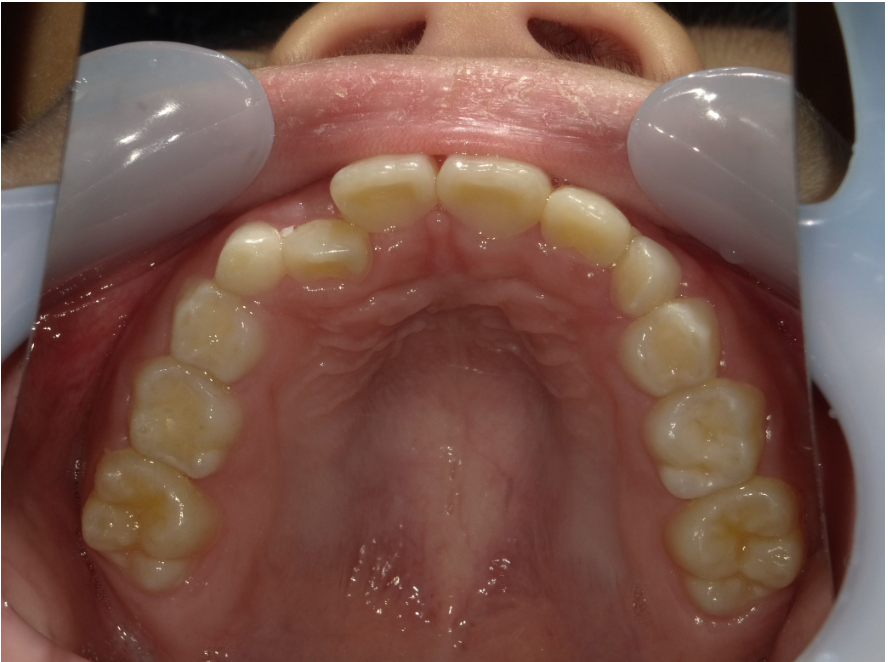

上顎

| 治療内容 | インビザライン・ファースト |

| 治療詳細 | スペース不足や交叉咬合を整えるために、歯の表面にアタッチメント(白い突起)をつけ、治療を行いました。 |

| 患者情報 | 9歳 男性 予防矯正から移行 |

| 主訴 | 永久歯は生えそろう十分なスペースがない 一部分だけかみ合わせが反対 |